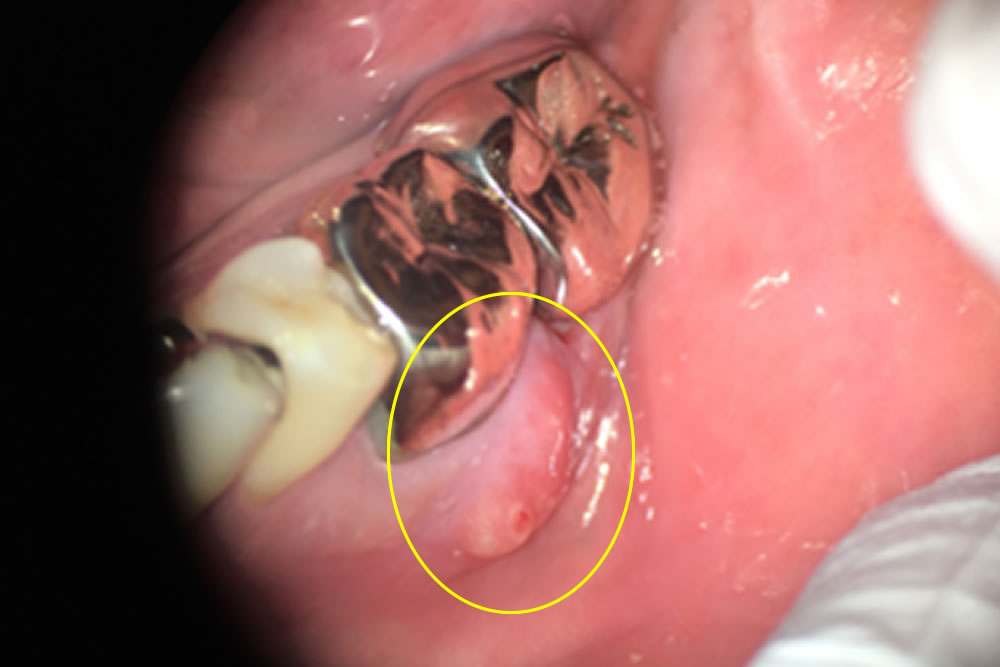

他院で抜歯と診断された歯を根管治療で保存した症例 こちらの患者さまは右下の歯が痛いとのことで来院されました。右下6~8は虫歯になっており、8番は抜歯、6、7番は頬側、舌側にフィステル(歯根の先端に起きる炎症が原因で歯茎に […]